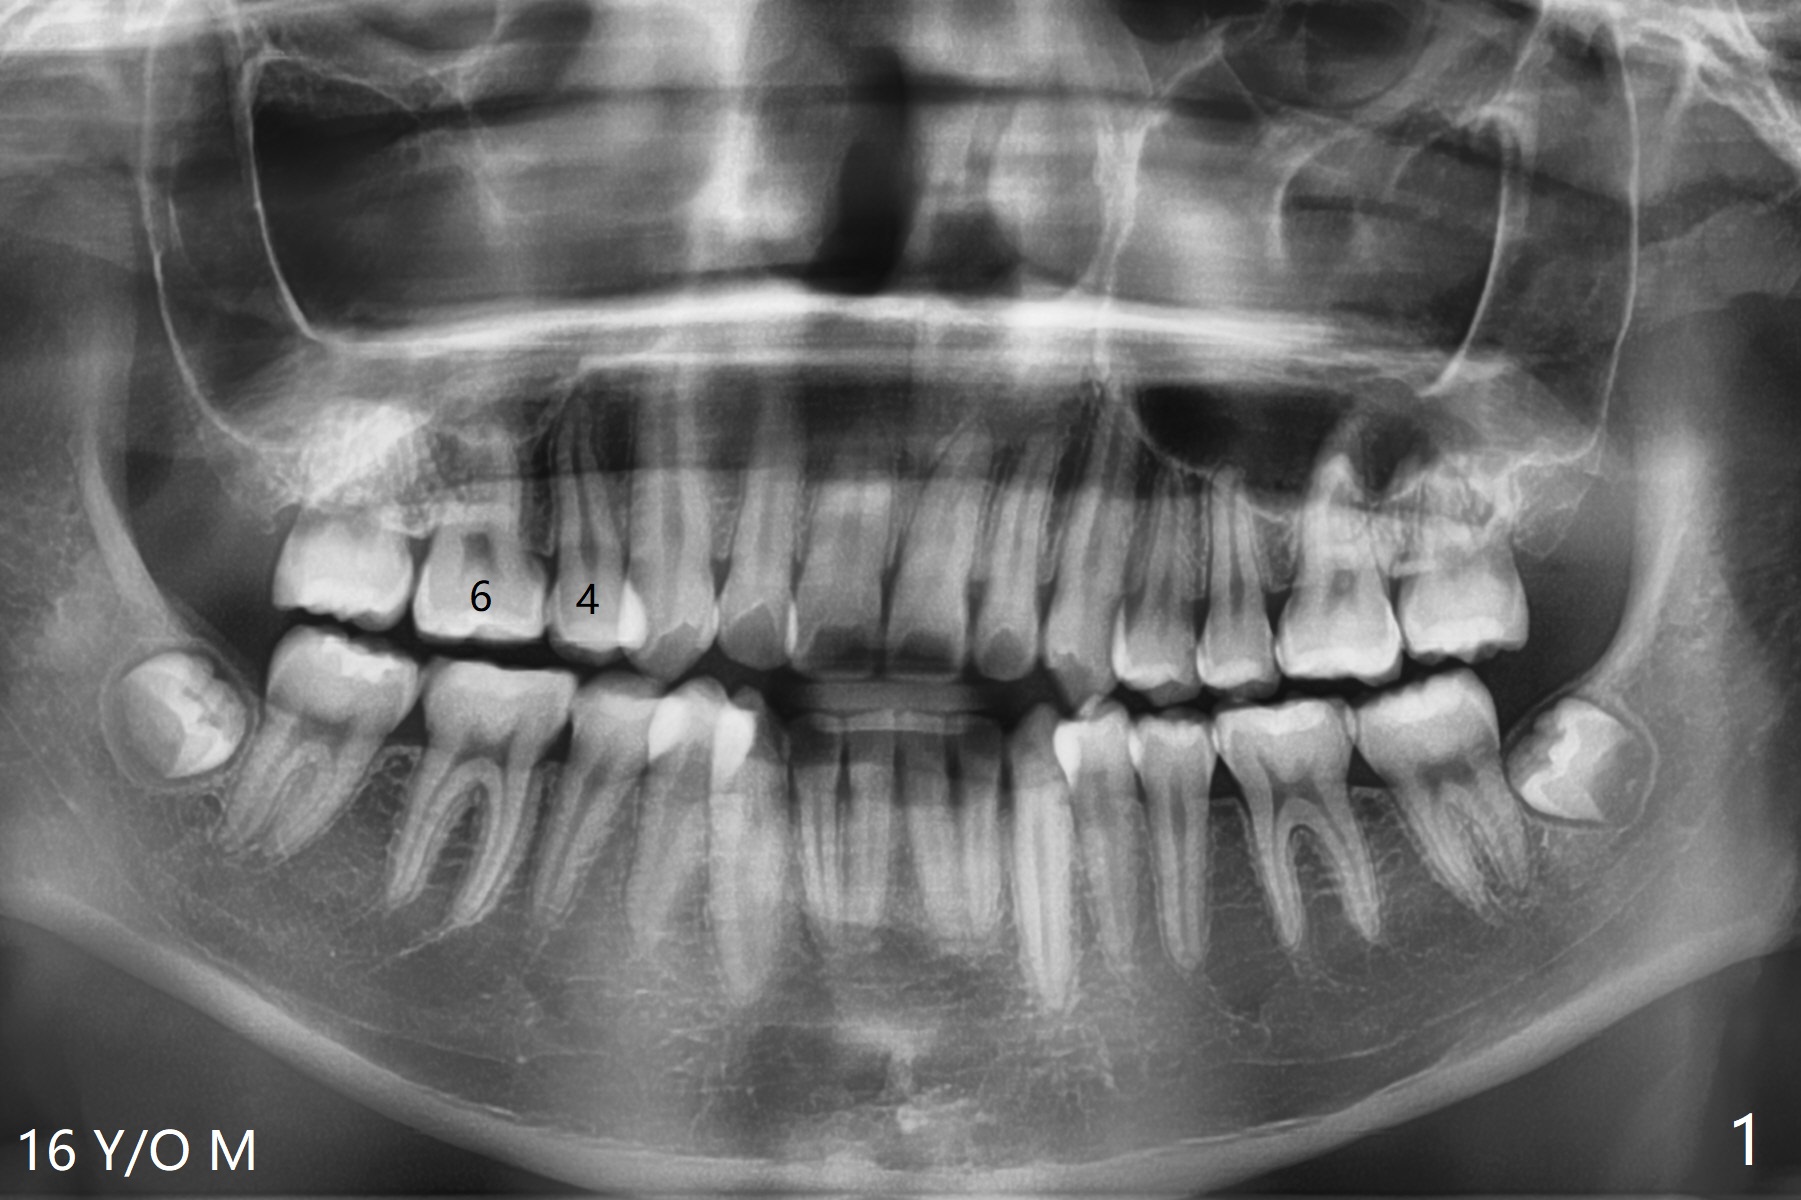

16岁男孩先天性缺失右上5,上牙中线偏右侧,下颌牙列拥挤,妈妈要求马上拔除智齿,减轻拥挤,可乎?